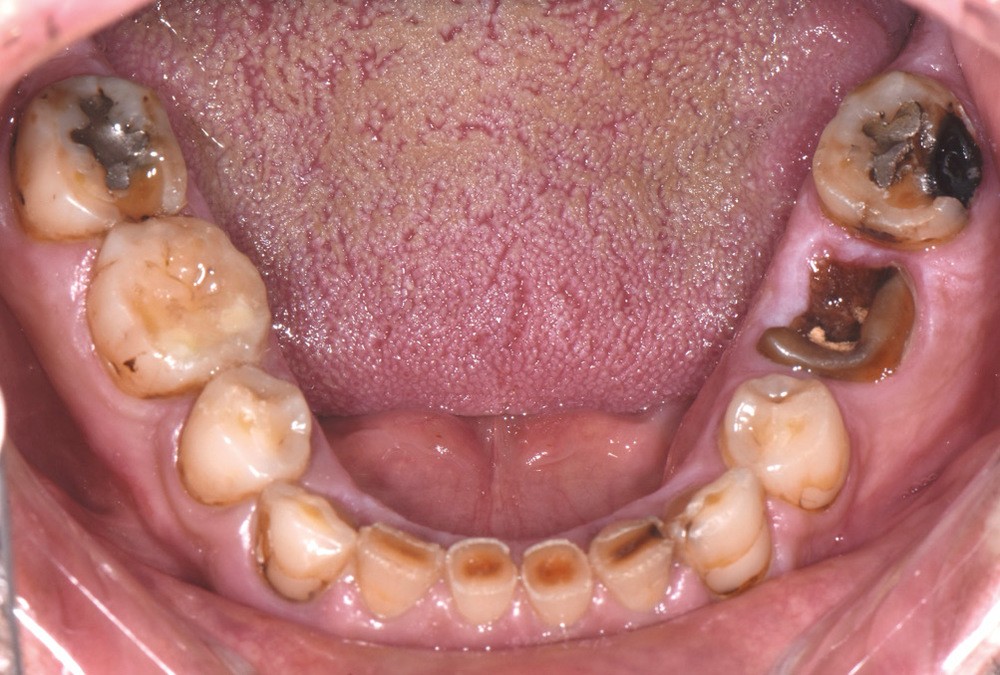

Au vu du contexte para-fonctionnel et de l’étendue de la perte tissulaire, des coiffes périphériques minimalement invasives ont été choisies afin de restaurer l’esthétique et la fonction. Actuellement, aucun consensus n’est fait sur le choix du matériau d’infrastructure à privilégier. Les matériaux hybrides usinables présentent des propriétés mécaniques, physiques et biologiques intéressantes en contexte d’usure sévère (e.g., module d’élasticité, résistance à la propagation de fêlures, facilité de réintervention). Une réhabilitation globale avec remontée de dimension verticale d’occlusion (DVO) par l’intermédiaire de coiffes composites renforcés en nano-céramiques est décrite.